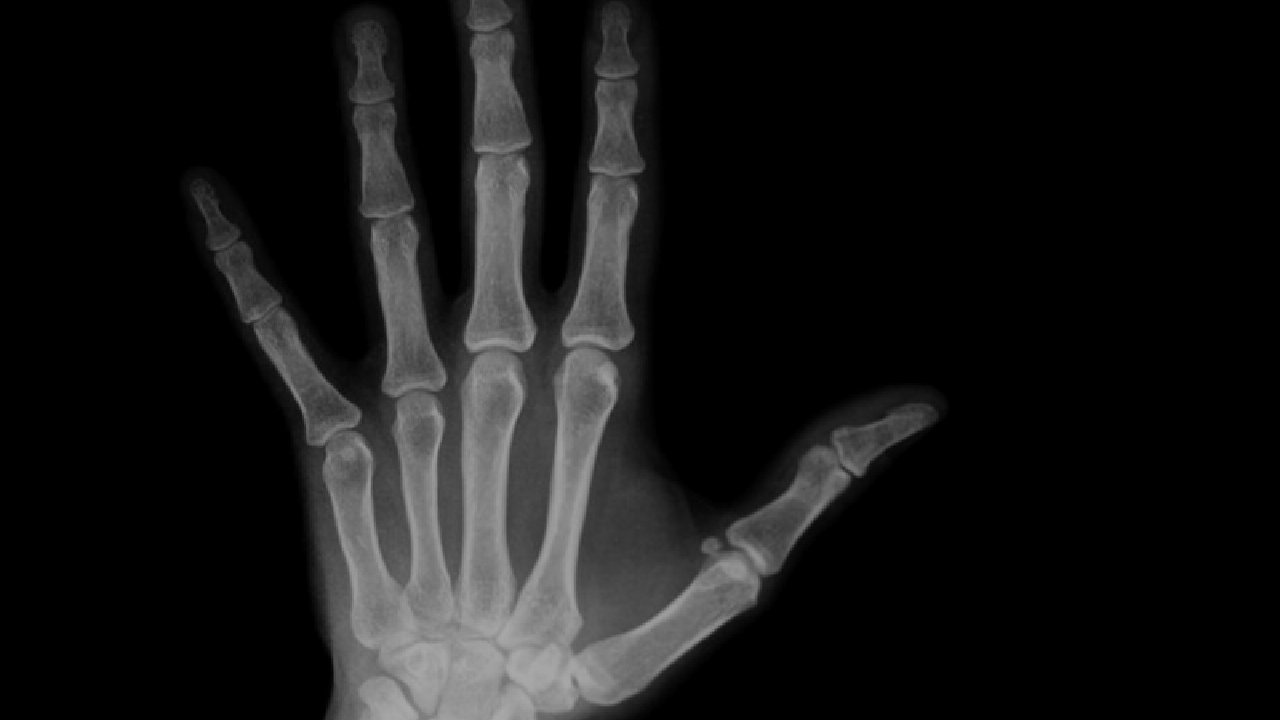

When you crack your joint, the dissolved gasses that are contained in the fluid are rapidly released. This causes a gas bubble, and the volume increases by 15 to 20%. In fact, if you take an x-ray, you can see this gas bubble, and you won’t be able to crack your knuckle again until the gas bubble dissolves back into synovial fluid.